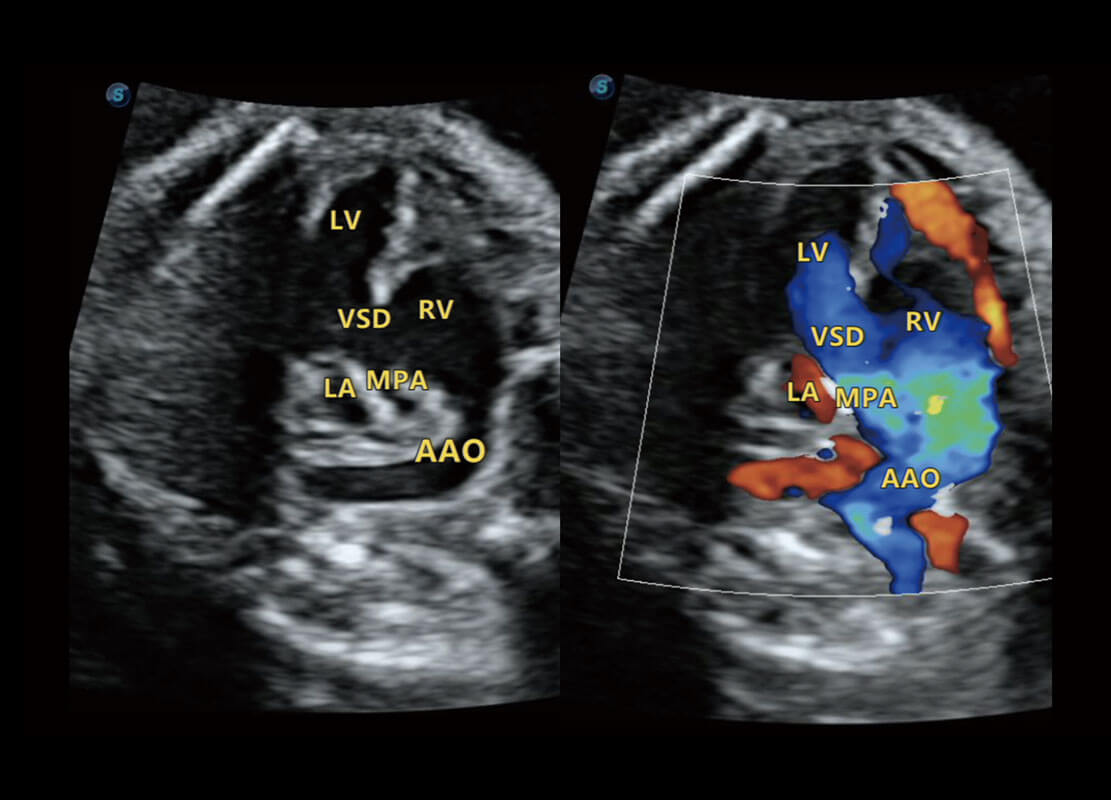

• 右室双出口

• 胎心容积成像